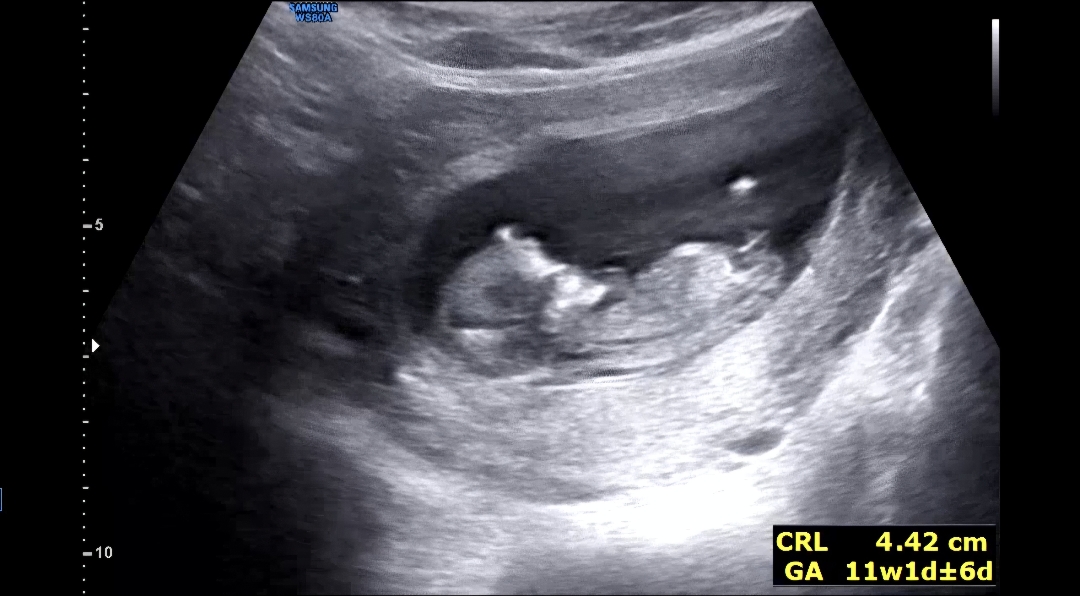

11주 3일 각도법 한번 봐주세용

각도법 고수님들 성별 한번 봐주세요~~!

딸인듯해요!

딸같아용